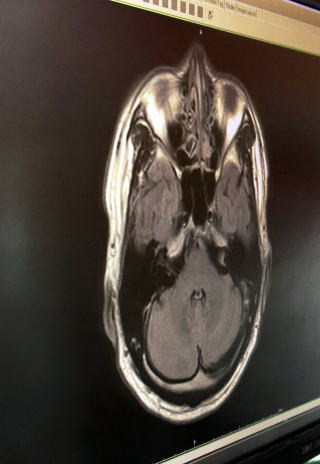

MRI検査初体験談です、いつも同じあたりに頭痛とその他

不調が長期に続いたので、病院の脳神経センターで問診と

なり頭から肩のMRI検査となったのです。

下の写真はMRIではなく、CTスキャン(≧。≦;)

初自分の脳みそとご対面、脳みそスカスカだったら、、、

脳神経医から見ると美しい脳だった様なのでので安心しました。

検査結果:腫瘍も癌も脳梗塞もなく、年齢にしても美しい脳ですと。

しかし気道(のど)がすこし狭くなっています、でした。

頭痛の原因は、粉塵症(PM2.5を含む日本風に言えば花粉症)

で目が開き辛いストレスが頭痛につながり、気道が狭いので発声

に影響していると思われます、薬を処方するので様子を見てくだ

さいと、再診日の予約票をいただきました。

おまけ編:何に見えますか?

私には、ゴジラと、仮面ライダーが見えました(≧▽≦)